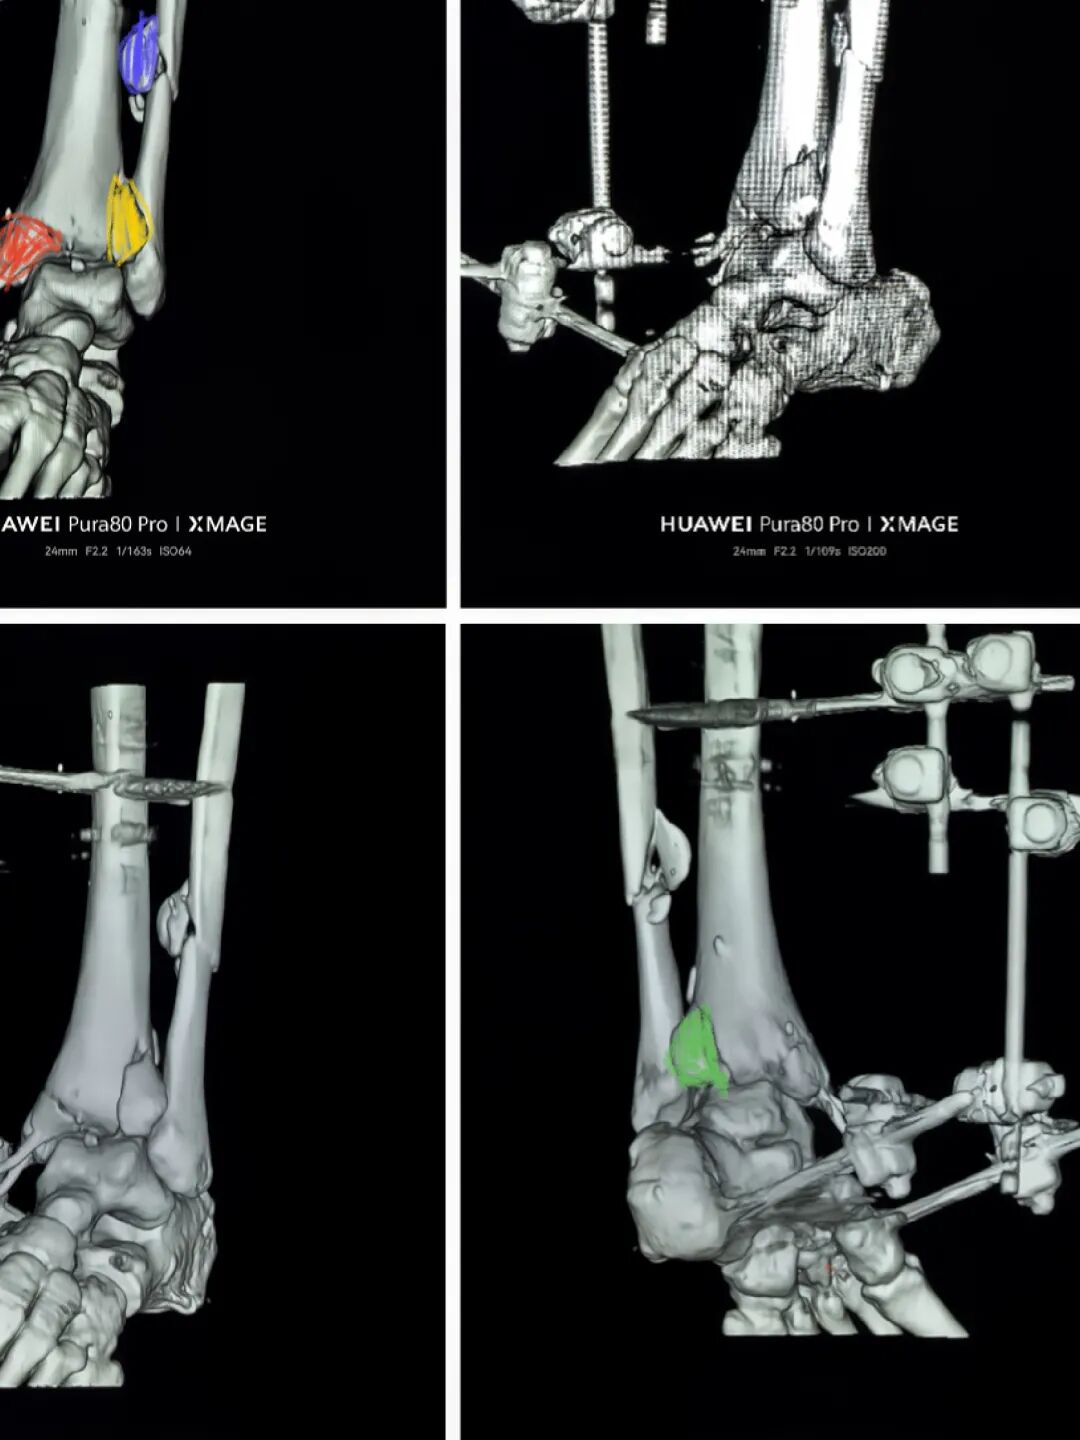

术后1周

行二次确定性手术

换钉子,调整下方向

解剖复位